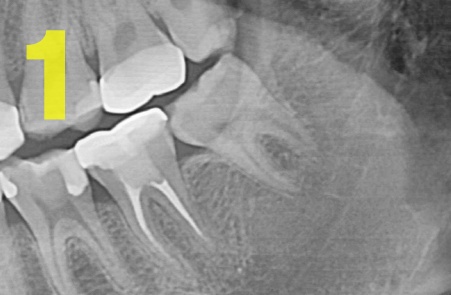

① 단순 매복 : 치조골(잇몸뼈) 속에 많이 묻혀 있지 않은 상태 (사진1)